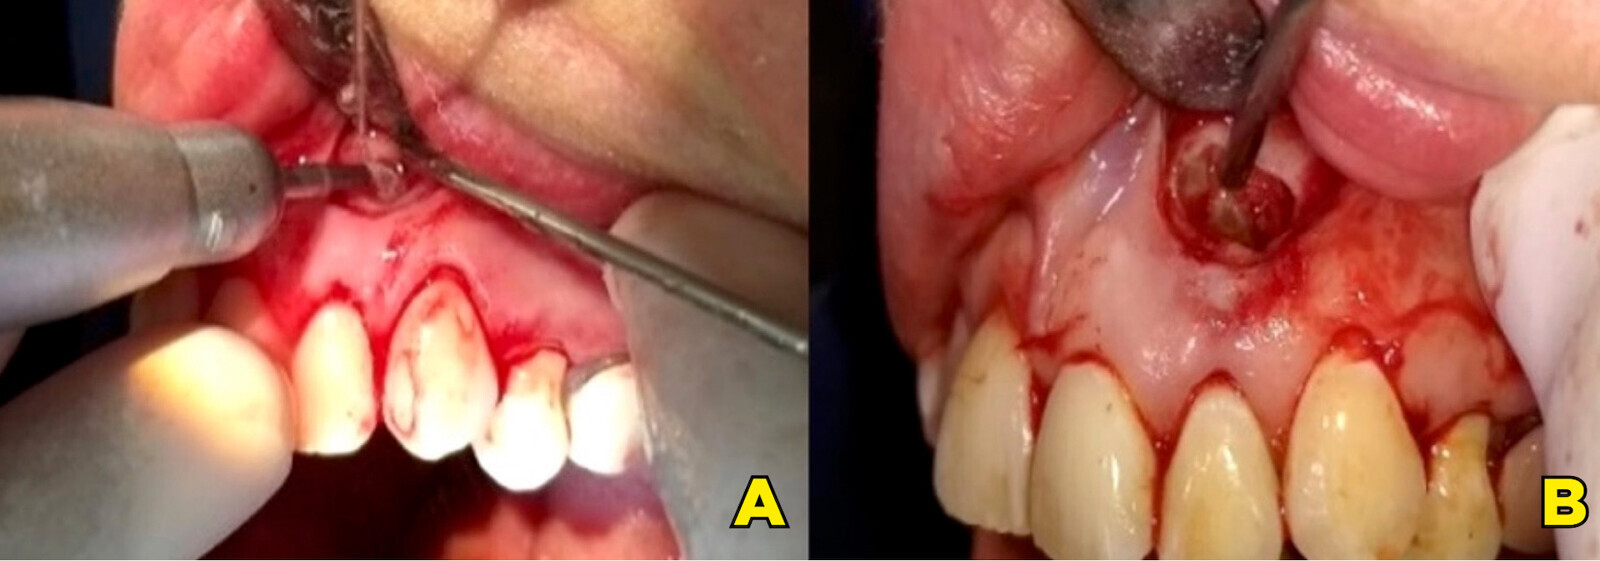

Figura 3. Osteotomía (A). Extirpación del material sobreobturado y remanente del periápice y posterior limpieza del lecho con legrado noble (B).

Figura 4. Procedimiento endodóntico empleando crioirrigación y obturando con sellado plastificado (A). El excedente fue contenido con una microesponja estéril para estabilizar y evitar diseminación, utilizando una técnica propia (B).

Figura 5. Verificación del empaque retrógrado (A) y obturación provisional de la cara palatina (B).